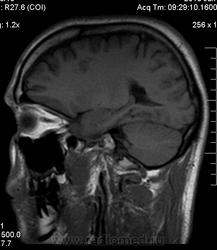

Мужчина 32 лет. Из анамнеза: перинатальное повреждение ЦНС, ДЦП, дизартрия, правосторонний верхний монопарез. С 16 лет приступы эпилепсии.

Аплазия прозрачной перегородки. Шизэнцефалия с открытыми краями в лобно-теменной области слева. Шизэнцефалия с закрытыми краями в лобной области справа? Утолщение коры по контуру расщелин и в области глазничной извилины правой лобной доли. Микрогирия? Гиперостоз костей свода черепа. Уважаемые коллеги, возможно я ошибаюсь, или есть еще аномалия?

На мой взгляд, полимикрогирия двусторонняя (конвекситальные отделы дорзальных отделов лобных долей и частично теменных, а также в базальном отделе полюса правой лобной доли) + закрытая шизенцефалия левой лобно-теменной области. Аплазия прозрачной перегородки (как признаки лобарной голопрозенцефалии).